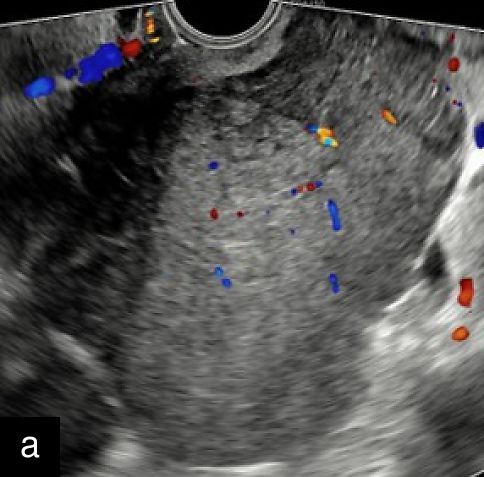

In 2019, an international group of experts conducted one of the first retrospective analyses of a relatively large cohort of histologically confirmed uterine sarcomas (n = 195; 116 LMS, 48 ESS and 31 USS), describing their most common ultrasound features.13 Malignant lesions appeared as large isolated solid masses (mean diameter, 91 mm) with inhomogeneous echogenicity of the solid tissue (77.4%), sometimes containing cystic areas (44.6%) (77% were irregular), mostly without fan-shaped shadowing or calcification (Figures 1 and 2). Although moderate-to-rich vascularization (color score 3–4) was common (67.9%), about one-third of sarcomas showed minimal or absent vascularization (color score 1–2), likely due to tumor necrosis (Figure 3). Notably, 20% were misclassified as benign, with ESS often showing normal endometrial appearance, regular margins and sparse vascularization, while USS displayed irregular margins, hemorrhagic cystic areas and absence of shadowing.13 One sarcoma was multilocular without solid components.13 The ‘cooked appearance’ of solid tissue, indicating necrosis, was observed in 21.7% of sarcoma cases13 but also appeared in leiomyomas and STUMPs, limiting its specificity.5 This sonographic feature refers to areas of inhomogeneous, hypoechoic solid tissue with absent internal vascularization, resembling the texture of cooked meat.

1

Transvaginal ultrasound images with Doppler evaluation of cases of STUMP. The images depict heterogeneous echotexture, irregular vascularization patterns and varying degrees of cystic and solid components.